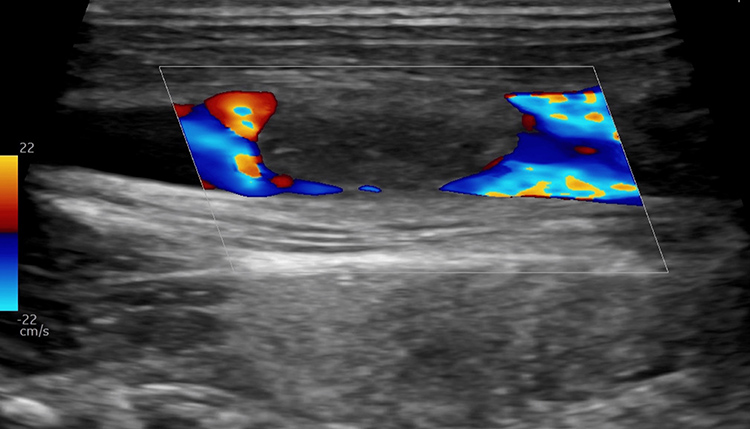

The differential diagnosis included bacterial and viral pharyngitis, acute mononucleosis, tick-borne illnesses (e.g., Ehrlichia, Rickettsia), Leptospirosis (given water exposure), and Lemierre syndrome (LS) secondary to Fusobacterium. Rapid Streptococcus pyogenes and Monospot® tests were negative, and throat culture later confirmed no Streptococcus pyogenes growth. Blood cultures (aerobic and anaerobic) were drawn. Doppler ultrasound revealed a nonocclusive right internal jugular vein (IJV) thrombus (Figure 1). Anaerobic blood cultures grew Gram-negative bacilli within 24 hours. Abdominal ultrasound showed mild hepatosplenomegaly and a minor left pleural effusion without inferior vena cava thrombus. Antibiotics were escalated to IV meropenem, and anticoagulation was initiated.

Figure 1: Neck ultrasound with Doppler in long axis view showing nonocclusive right internal jugular vein thrombus.